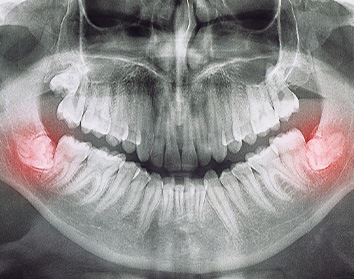

In short, wisdom teeth are the third set of molars. They typically make an appearance in a person’s late teens or early twenties. With that said, there are some patients who don’t develop them at all! That’s why it’s so important for our dentist in Morgan Hill, Dr. Hong, to take new X-rays every year. This ensures that she can monitor what’s going on underneath the gumline and, if necessary, perform an extraction.

- Not have sufficient room to erupt past the gumline, becoming impacted (stuck) and causing pain.

- Only emerge partially, making them difficult to clean and increasing the risk of tooth decay and infections.

The extraction process will look a bit different depending on whether or not the tooth in question is trapped underneath the gumline. If that’s the case, then an incision needs to be made in the gums first. Then, the tooth can be removed section by section, and we can tend to the extraction site. Conversely, if the tooth has already broken through the gumline, then we can simply grip it, rock it loose, and remove it.